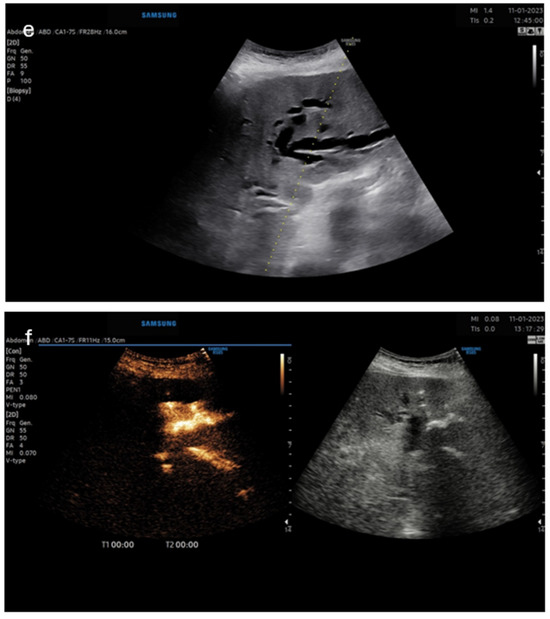

Figure 4. Panel (e)—B-mode image of planning the puncture site; panel (f)—dual image—left CEUS image, right—B-mode.

The third case was a female patient with an inoperable Klatskin tumor (Figure 4). ERCP showed >90% malignant stenosis of ductus choledochus at the hilum with a length of 20 mm. The patient was referred for PTCD, and the proper drainage catheter position in the bile ducts of the left liver lobe was confirmed by intracavitary CEUS: